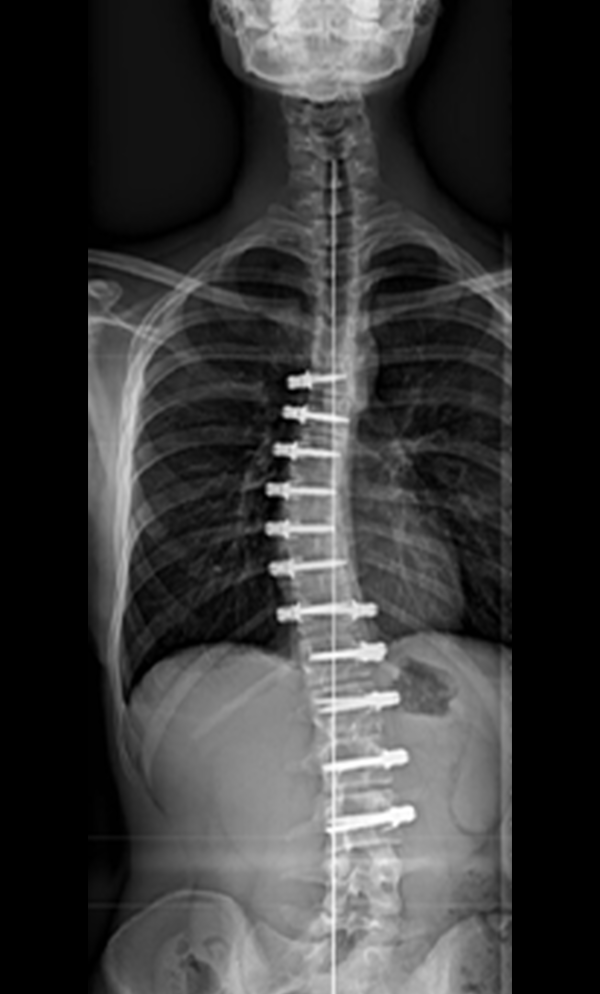

Gallery : Before - After